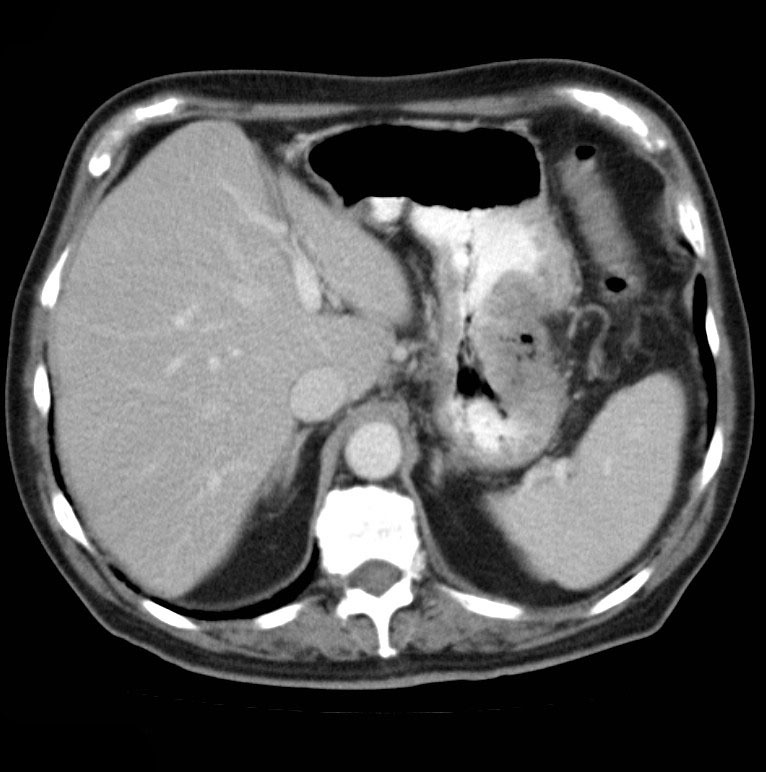

The pancreas appears bulky and shows an ill-defined isodense hypoenhancing mass measuring approximately 4.3 x 2.0 cm. There is extensive polypoidal thickening of upper gastrointestinal tract wall, involving the pylorus of stomach, duodenum, jejunum and proximal ileum. The polyps measure 5 to 30 mm and causing luminal compromise. The proximal small bowel appears distended till distal ileum and there is an ileo-ileal intussusception noted in the distal ileum. The terminal ileum and large bowel appear collapsed.

There are few enlarged non-necrotic lymph nodes noted in the mesentery, the largest lymph node measures 1.3 x 0.8 cm in size. There is a well defined oval mass measuring approximately 6.0 x 4.5 cm noted in the right adnexa. The right ovary could not be separately visualized from the mass. The mass shows post contrast enhancement and central non-enhancing necrotic region within.

Extensive polypoidal mucosal thickening predominantly affecting the upper gastrointestinal tract with pancreatic and ovarian neoplasms are likely to represent gastrointestinal polyposis syndrome most likely Peutz Jeghers Syndrome.